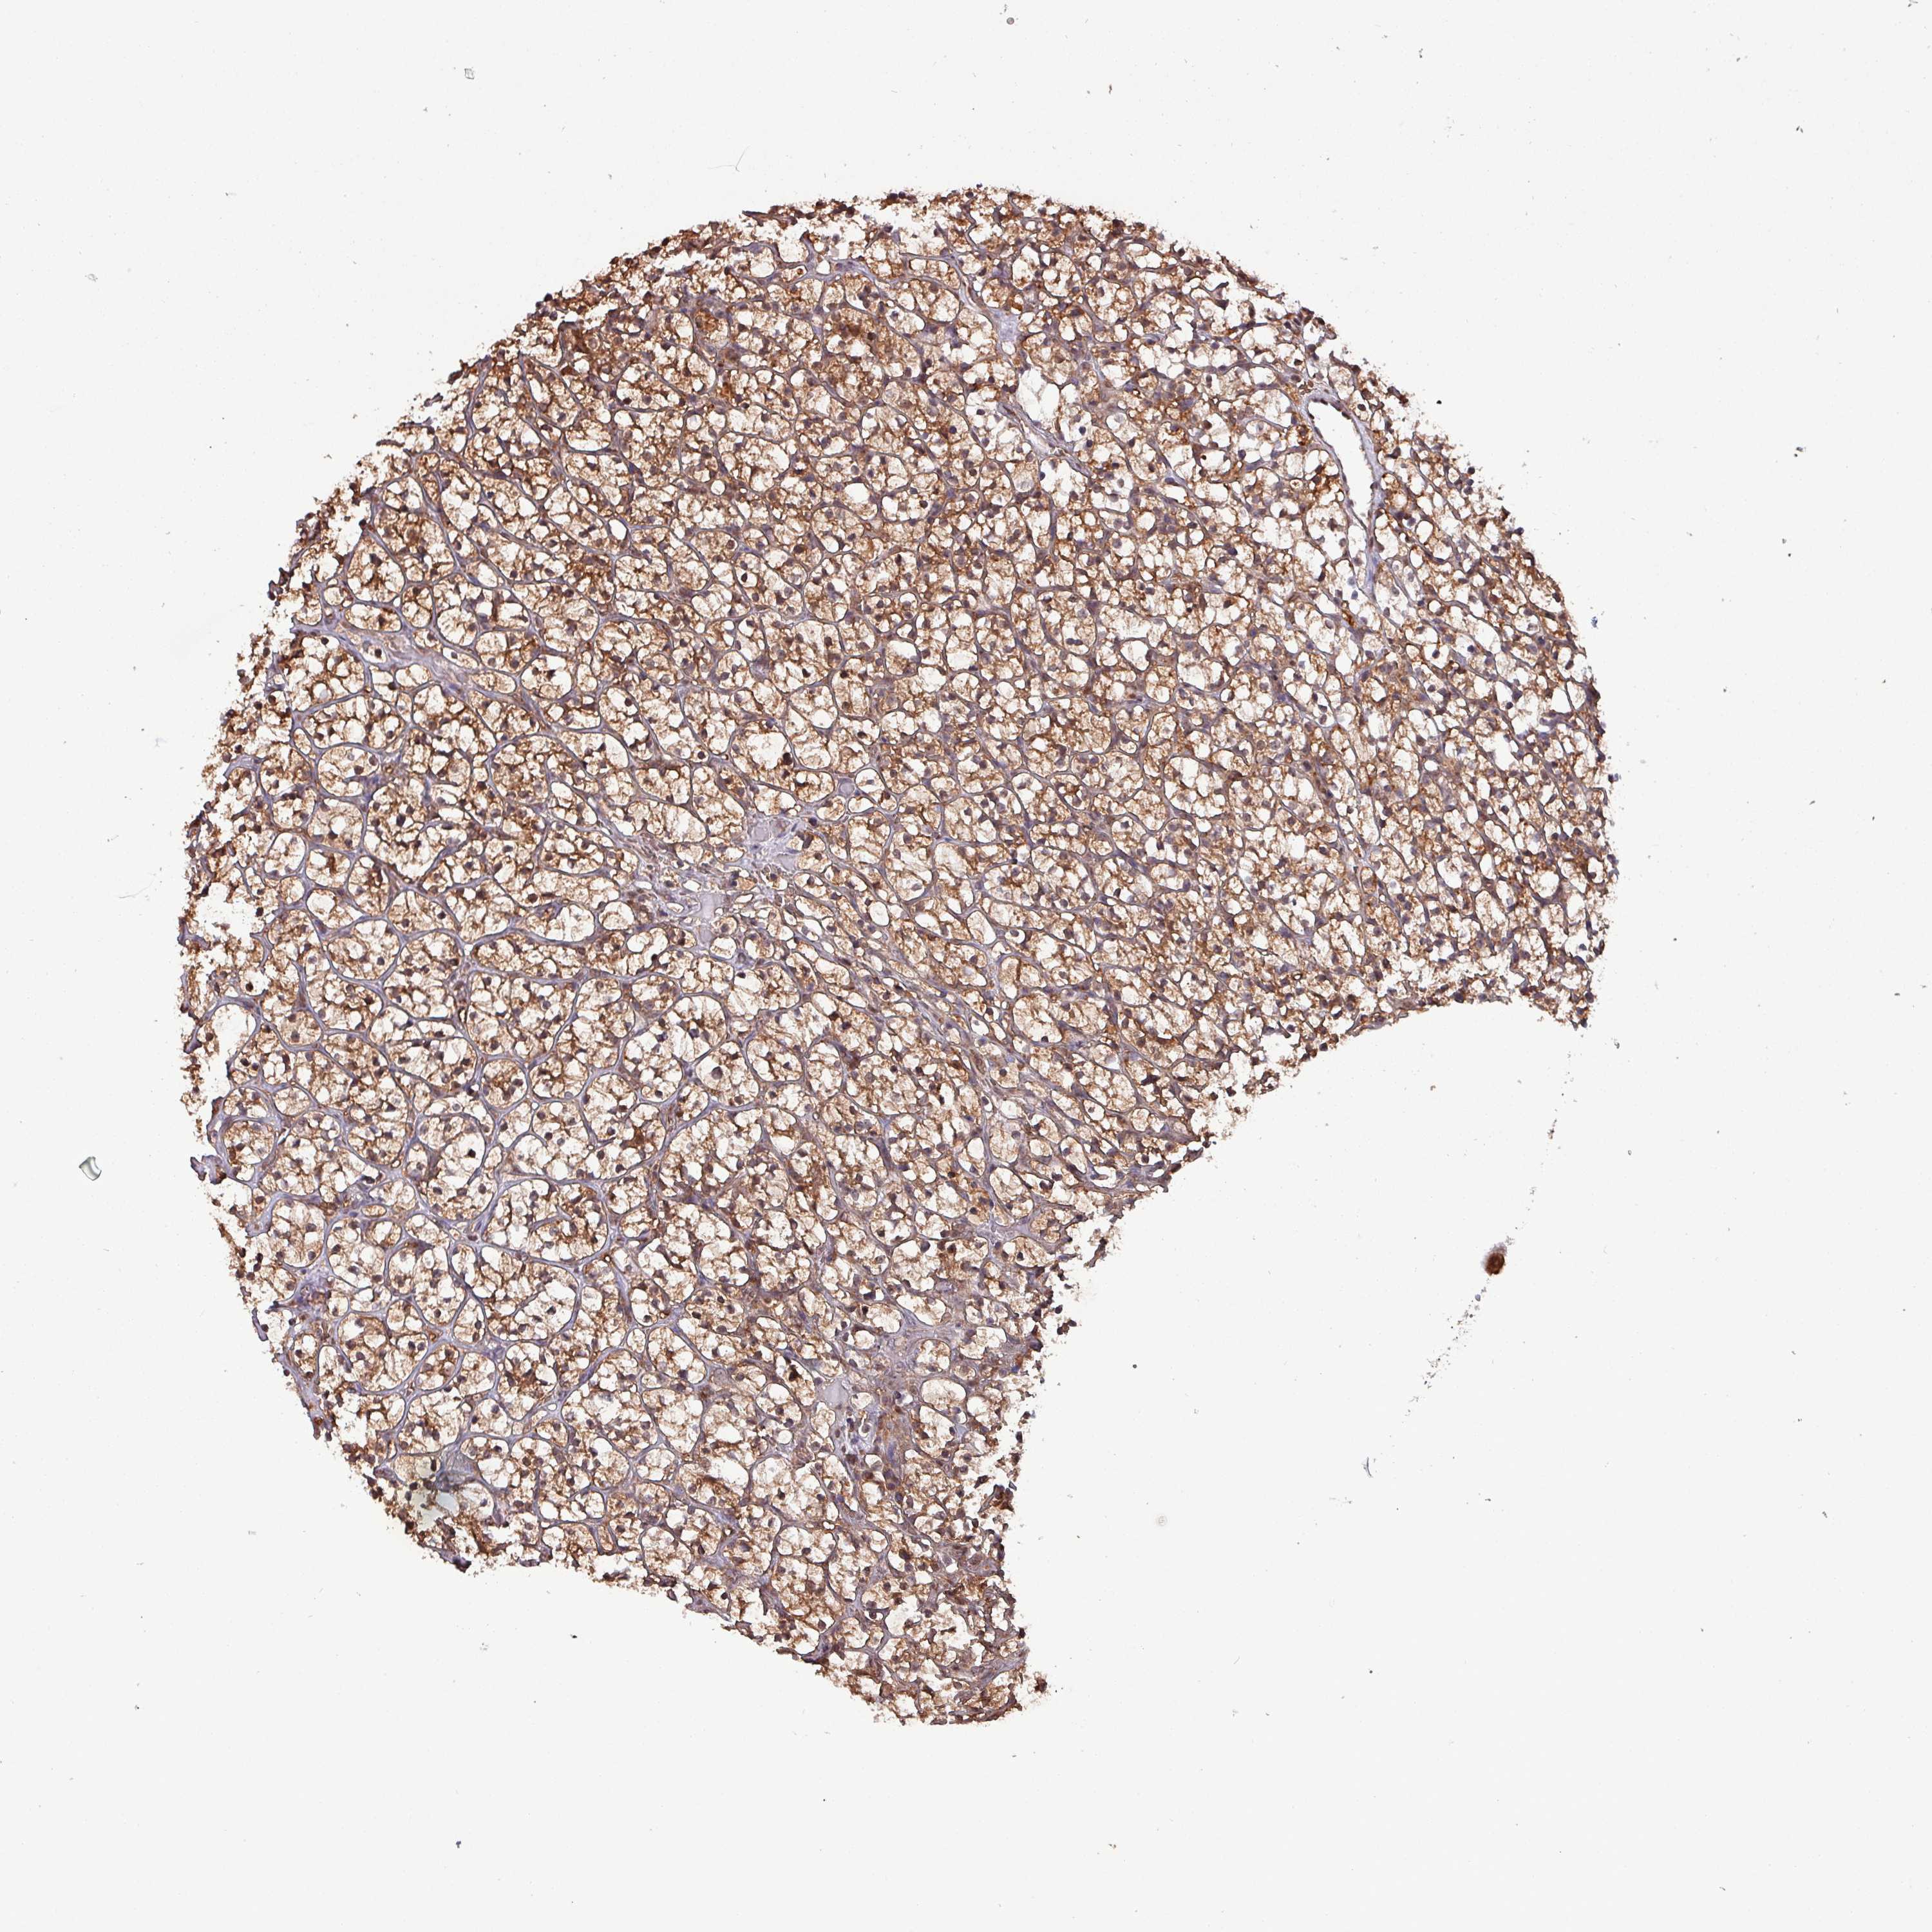

KIDNEY RENAL PAPILLARY CELL CARCINOMA (TCGA) - Interactive survival scatter ploti

The Survival Scatter plot shows the clinical status (i.e. dead or alive) for all individuals in the patient cohort, based on the same data that underlies the corresponding Kaplan-Meier plots. Patients that are alive at last time for follow-up are shown in blue and patients who have died during the study are shown in red.

The x-axis shows the expression levels (FPKM) of the investigated gene in the tumor tissue at the time of diagnosis. The y-axis shows the follow-up time after diagnosis (years). Both axes are complimented with kernel density curves demonstrating the data density over the axes. The top density plot shows the expression levels (FPKM) distribution among dead (red) and alive patients (blue). The right density plot shows the data density of the survived years of dead patients with high and low expression levels respectively, stratified using the cutoff indicated by the vertical dashed line through the Survival Scatter plot. This cutoff is automatically defined based on the FPKM cutoff that minimizes the p-score. The cutoff can be changed by dragging the vertical line or by entering a cutoff value in the square labeled "Current cut-off".

Under the Survival Scatter plot the p-score landscape (black curve; left axis) is shown together with dead median separation (red curve; right axis). Dead median separation is the difference in median mRNA expression between patients who have died with high and low expression, respectively. It is calculated as follows: median FPKM expression of dead patients with high expression - median FPKM expression of dead patients with low expression. This is intended to aid the user in visually exploring custom cutoffs and the associated p-scores and dead median separation.

Individual patient data is displayed and can be filtered by clicking on one or more of the category buttons on the top of the page. Categories describing expression level and patient information include: high, low, alive, dead, female, male and tumor stages. The scale of the x-axis can be toggled between linear and log-scale by clicking on the "x log" button. Mouse-over function shows TCGA ID, patient information and mRNA expression (FPKM) for each patient.

& Survival analysisi

Kaplan-Meier plots summarize results from analysis of correlation between mRNA expression level and patient survival. Patients were divided based on level of expression into one of the two groups "low" (under cut off) or "high" (over cut off). X-axis shows time for survival (years) and y-axis shows the probability of survival, where 1.0 corresponds to 100 percent.

PSMB8 is not prognostic in Kidney Renal Papillary Cell Carcinoma (TCGA)